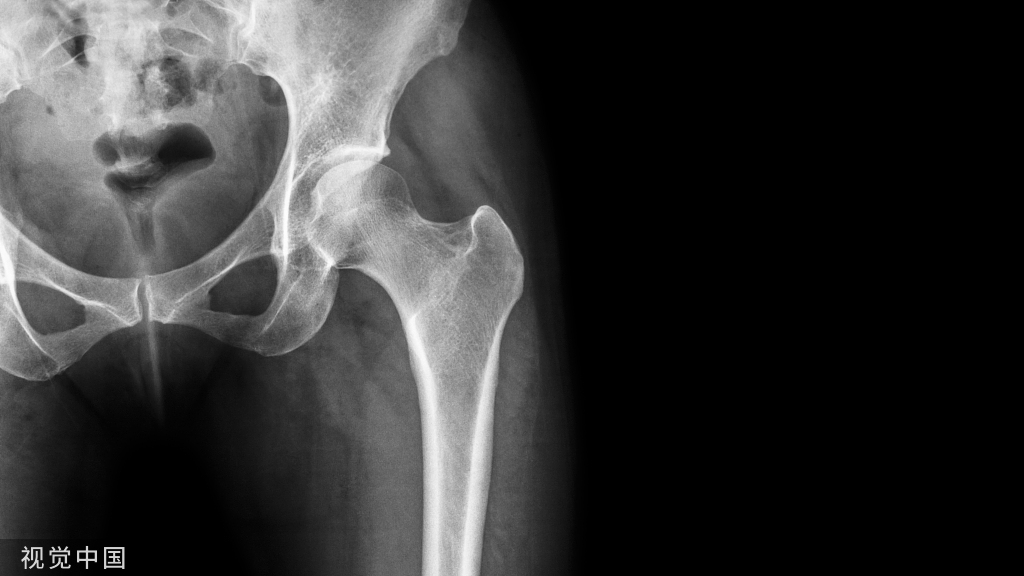

术前准备X线检查,确认骨折愈合